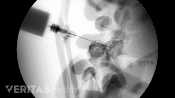

Injections relieve neck and back pain by delivering medications directly to the affected area, reducing inflammation.